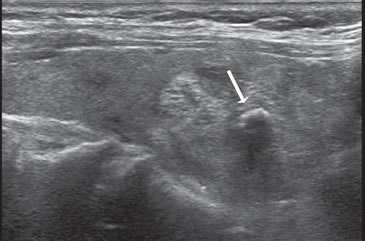

Otro aspecto con muy alta probabilidad de malignidad21 es el de un nódulo sólido relativamente hipoecogénico, con margen mal definido e infiltrativo, con múltiples microcalcificaciones periféricas (Figura 29) y/o microcalcificaciones difusas que aumentan la ecogenicidad de la lesión (Figura 30).

Figura 29. Cáncer papilar de bordes infiltrativos hipoecogénico con

múltiples microcalcificaciones en la zona periférica (flechas).